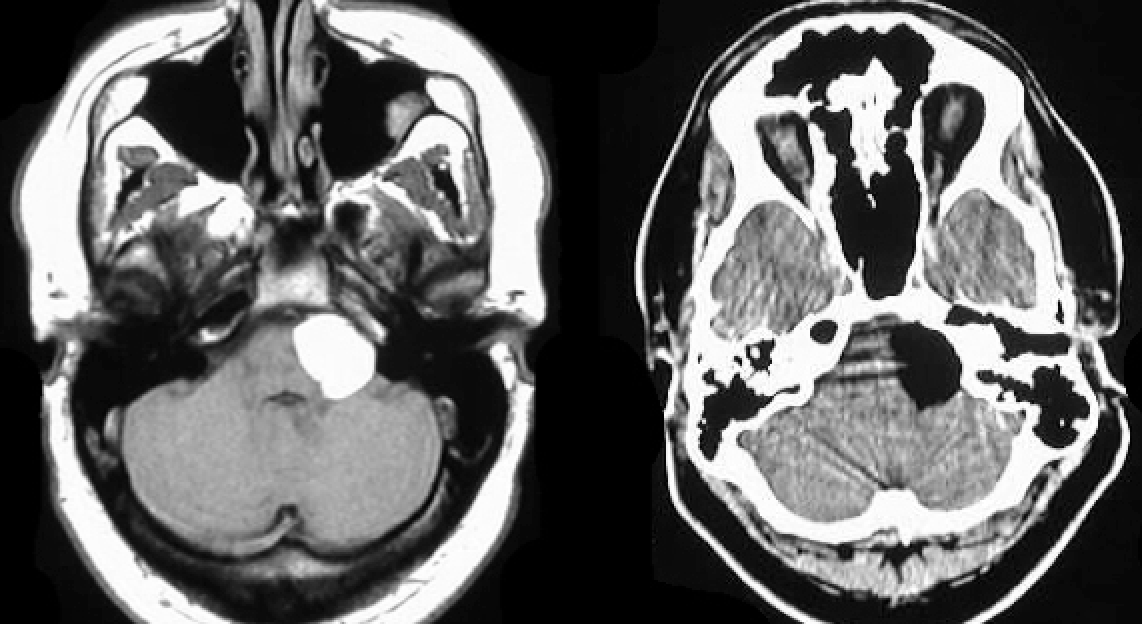

Otherwise well baby with macrocephaly

Imaging abnormality and likely etiology?

Hydrocephalus and congenital aqueductal stenosis

Large lateral ventricles with “dangling choriod plexus sign”

Dysmorphic baby

Diagnosis?

Holoprosencephaly

(often associated with missing nose, single eye, and other midface abnormalities)

Large monoventricle, fused thalami, absence of falx

(thanks to Raf Llinas)

Baby born to mother with hypercoagulable disorder

Etiology?

Hydranencephaly

No cerebral hemispheres visualized

but Falx, thalami, and midbrain are intact

In-utero ACA and MCA strokes